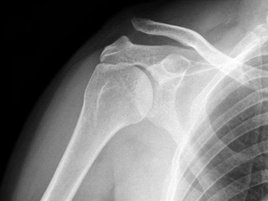

Діагноз вивиху акроміального кінця ключиці

Діагноз вивиху акроміального кінця ключиці іноді дуже простий і все очевидно при огляді, а іноді доводиться вирішувати цілу головоломку. Найбільш оптимальним і поширеним способом діагностики є рентгенографія. Варто сказати, що, як не буває однакових людей, так і не буває однакових ключиць. Найчастіше причиною помилкового діагнозу індивідуальні особливості акромиально-ключичного суглоба.

Тому доцільно виконувати рентгенограму не одного плеча, а двох відразу - що дозволить оцінити нормальну будову протилежної ключиці.

Рентгенографія - діагностика при вивиху акроміального кінця ключиці

У сумнівних випадках іноді виконують функціональну рентгенографію - в руку беруть вантаж, який відтягує її вниз і вивих стає більш очевидним.